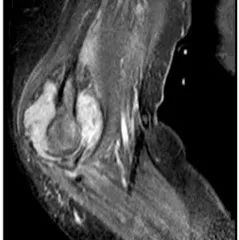

单关节疼痛不属于类风湿?「标准」也有出错的时候……

*仅供医学专业人士阅读参考你在临床上见过这种情况吗?类风湿关节炎是一种以对称性炎症性多发性关节炎为特征的慢性自身免疫性疾病。现有的2010年美国风湿病学会/欧洲抗风湿病联盟(ACR/EULAR)的标准系统不考虑仅限于单个大关节的关节炎。而最近BMJ Case Reports上就报告了一例中年女性经滑膜组织活检证实的肘部单关节类风湿关节炎。“标准之外”的单关节类风湿关节炎,到底有什么特别?一起来看看吧。...